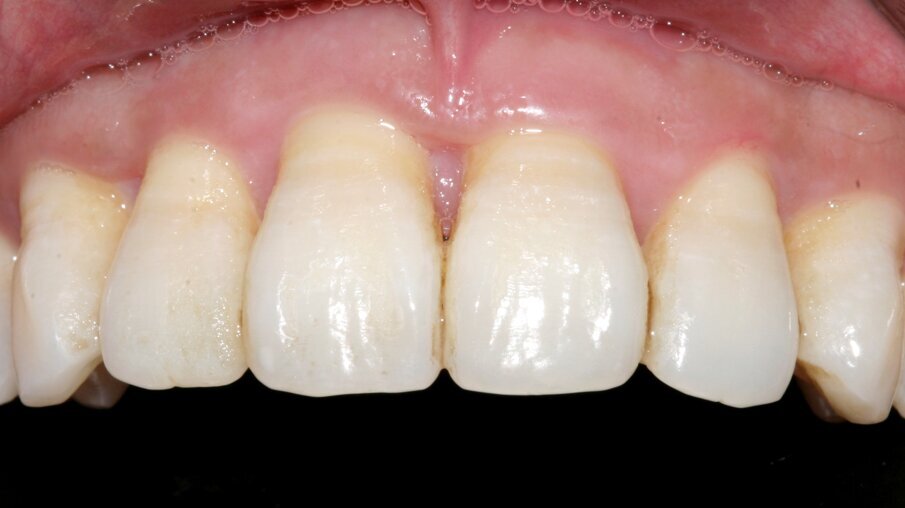

Fig. 1: Area amenable to grafting with CAPD

Fig. 4: 1 yr clinical photo demonstrating excellent periodontal health, with 2mm pocket depth, and increased zone of KG, with increased buccal bone support